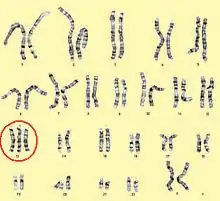

Chromosome 8

_chromosome_abnormality.jpg.webp)

Tetrasomy and hexasomy 8 are rare compared to trisomy 8, which is the most common karyotypic finding in acute myeloid leukemia (AML) and myelodysplastic syndromes (MDS).[24] AML, MDS, or myeloproliferative disorder (MPD) with a high incidence of secondary diseases and a six-month survival rate are associated with a polysomy 8 syndrome.[25]

Giemsa banding (G-banded karyotyping)

Karyotypes are commonly analyzed using Giemsa banding (G-banded karyotyping)). Each chromosome shows unique light and dark bands after they are denatured with trypsin and polysomies can be detected by counting the stained chromosomes. Several cells have to be analysed to detect mosaicism.[53]